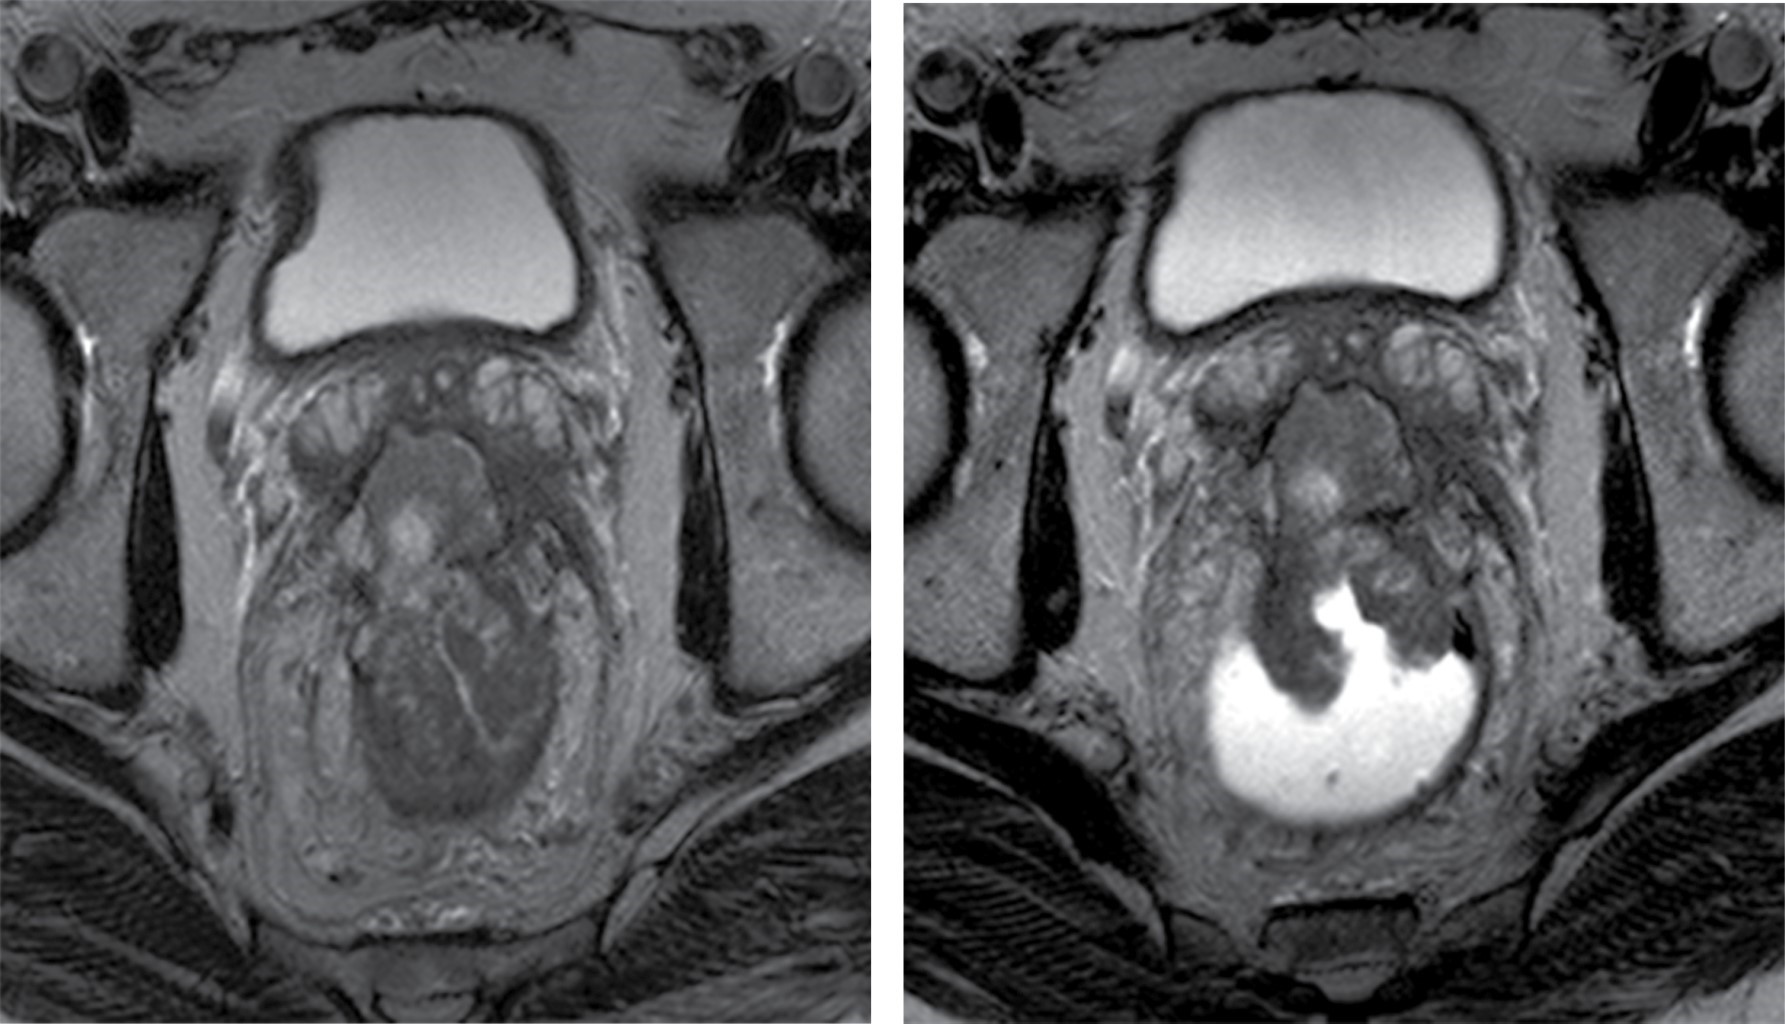

Paciente masculino de 64 años de edad, sin antecedentes personales de importancia, que hace aproximadamente seis meses presenta cambios en los hábitos intestinales con periodos de estreñimiento y diarrea que se acompañan de heces acintadas y rectorragia, por lo que acude a médico tratante quien envía resonancia magnética para valoración de recto.

En el caso expuesto se realizó un protocolo de resonancia magnética con secuencias de T2, difusión, ADC y administración de gadolinio en planos axial, sagital y coronal con y sin la aplicación de gel endorrectal, obervándose los hallazgos descritos en las Figuras 1, 2 y 3; características que se valoran con exactitud y gran detalle anatómico, requerimientos indispensables para una correcta estadificación.

Se catalogó esta lesión como T4aN1b.

Figura 1

Figura 2